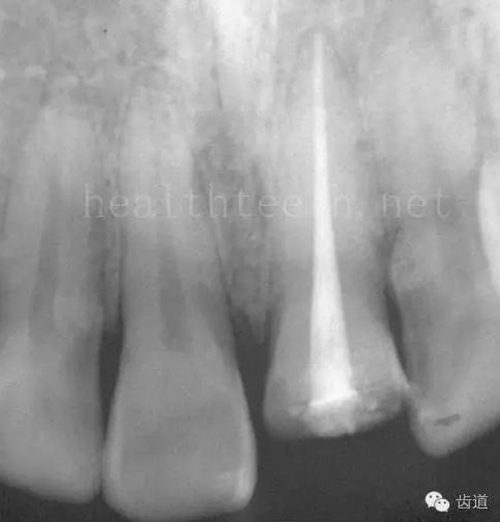

八、牙髓炎、根尖周炎

下面圖片都是慢性根尖周炎的病例,有了齲齒,進(jìn)一步發(fā)展就是牙髓炎,如果此時(shí)沒(méi)有得到及時(shí)的治療,疾病會(huì)逐漸發(fā)展破壞到根尖的骨質(zhì),將骨質(zhì)破壞后就在牙齦上出現(xiàn)一個(gè)膿瘺,此時(shí)患者不再感覺到牙齒的疼痛了,往往忽視了治療,但是這種不痛并不是疾病好轉(zhuǎn)了,而是因?yàn)榧膊〉难仔詽B出得到了引流,這個(gè)膿瘺會(huì)出現(xiàn)有時(shí)候變大了,有時(shí)候又變小了,但是如果不治療是不會(huì)自己愈合的,只有經(jīng)過(guò)完善的根管治療后才有好轉(zhuǎn)的可能,但是在疾病的治療中時(shí)間是起決定作用的,時(shí)間拖得越晚,好轉(zhuǎn)的可能性越小,經(jīng)過(guò)根管治療后如果膿瘺還是沒(méi)有消失,就需要做根尖刮治術(shù),如果仍然沒(méi)有好轉(zhuǎn),就只能做根尖切除術(shù)了,這對(duì)牙齒的穩(wěn)固是不利的。下面圖片中在膿瘺中插入了一個(gè)牙膠尖,是我們做根管充填用的材料,是非常軟的,就是在口腔牙齦瘺管的地方插進(jìn)去,通過(guò)拍牙片可以清晰地看到它到達(dá)的位置,從而確定發(fā)病的牙齒,此處是為了讓大家看得更清楚。

門牙兩個(gè)膿瘺

69.jpg

烤瓷牙修復(fù)后牙齦出現(xiàn)兩個(gè)膿瘺,插入牙膠尖,牙片顯示牙膠尖到達(dá)的位置就是根尖炎癥的位置,根尖骨質(zhì)密度降低(發(fā)黑的地方)